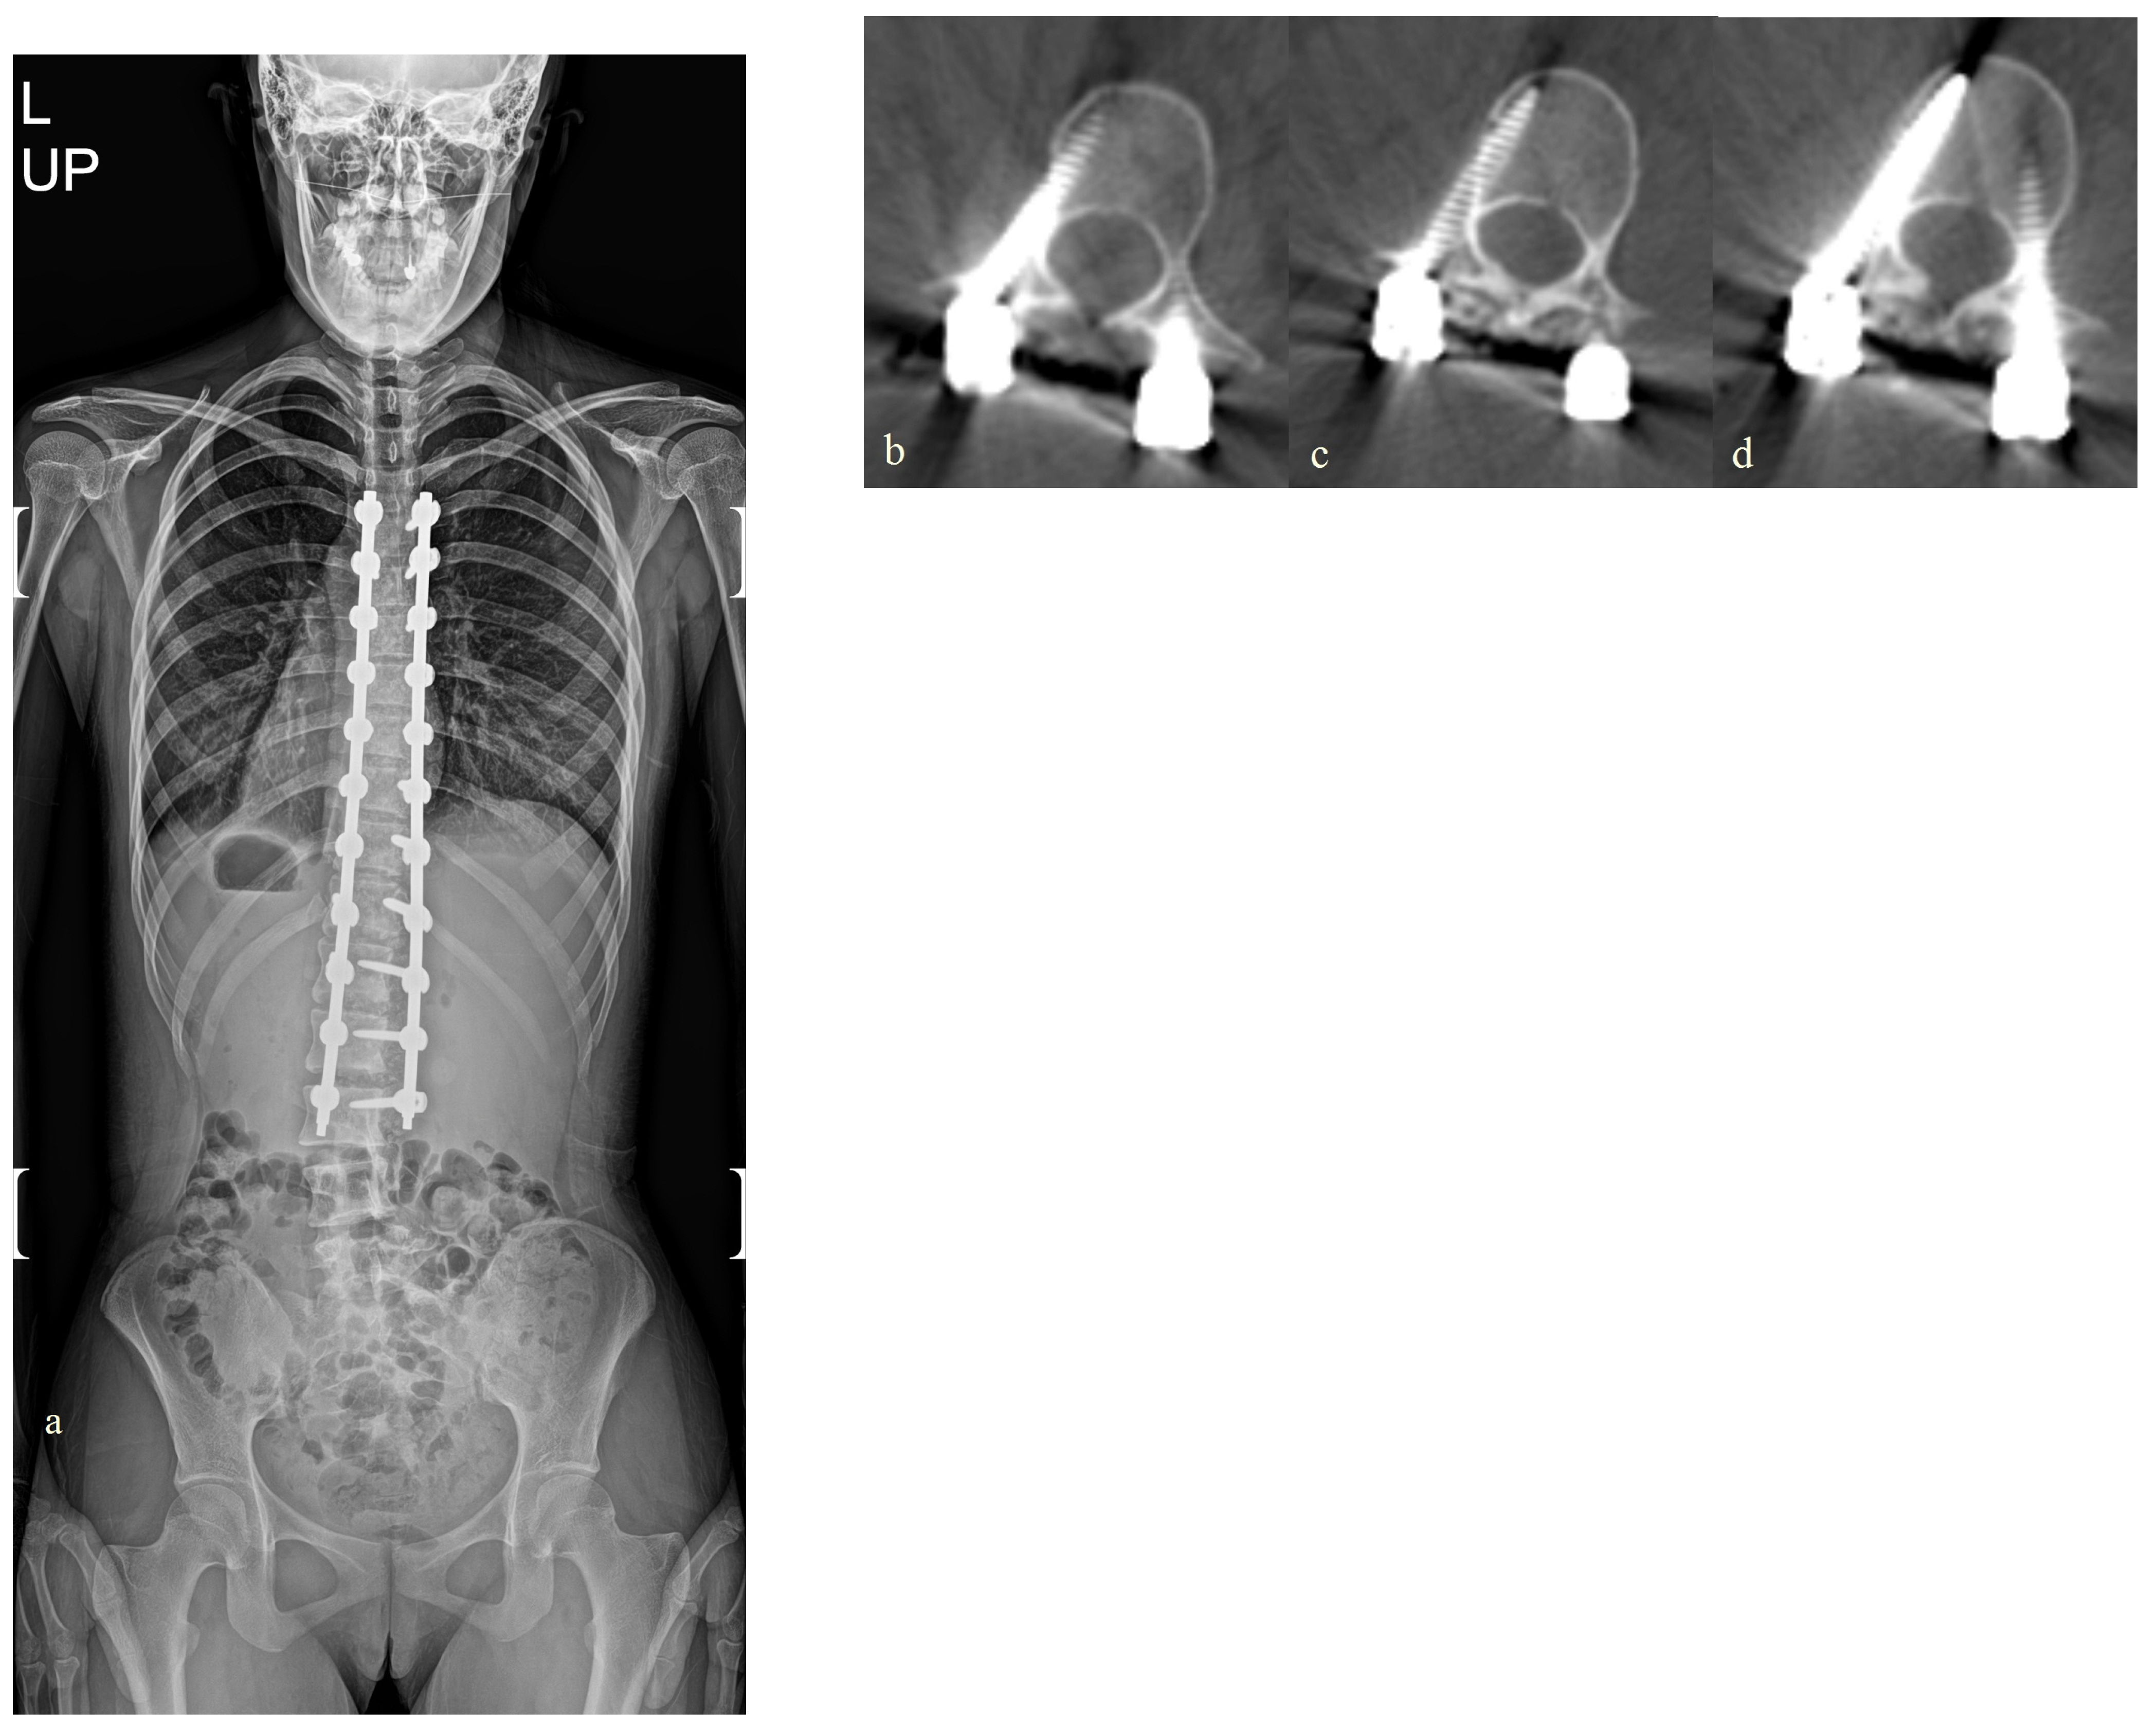

| L | 10/F | Marfan scoliosis | L1 | 28 | 71 | 50 | 41 | ||

| L2 | 22 | ||||||||

| L | T2-L4 | T9-L2 | L1, 1ea | 5.5 × 35 |

| L2, 1ea | 5.5 × 45 | |||